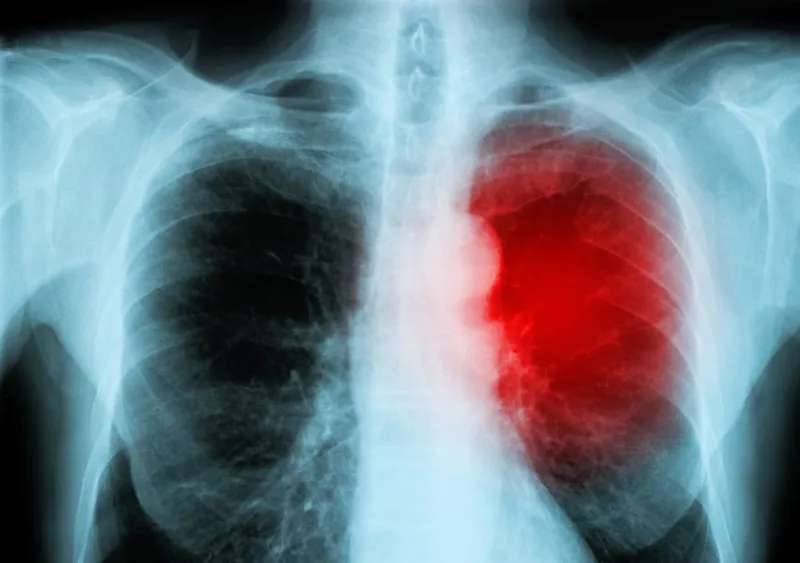

Une pleurésie

2/10

red heart of a human x-ray image from a human body part, for medical disease diagnosis ideal for websites and magazines layouts

Istock

Le tissu qui tapisse votre poitrine et entoure vos poumons peut s'enflammer pour de nombreuses raisons. Cette affection est appelée "pleurésie".

Selon l'endroit où se trouve l'inflammation, elle peut ressembler à des brûlures d'estomac, mais elle s'aggravera lorsque vous respirerez, toussez ou éternuez. Certaines personnes ont également de la fièvre.

Si vous avez une pleurésie, votre médecin devra traiter sa cause. Il peut également vous aider à gérer la douleur.